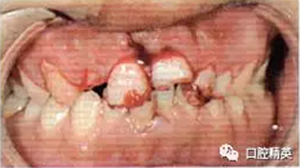

2冠根折,唇側(cè)斷端至齦下2mm,露髓,叩痛(+),不松,齦緣滲血;1冠折,未露髓,部分脫出,叩痛(+),松Ⅲ度,近中齦乳頭撕裂,長約1.5 cm;1挫入,切斷折斷,位于拉冠中部,叩診高調(diào)金屬音,不松,近中齦乳頭撕裂,長約1.5 cm;2見釉質(zhì)裂紋,叩痛(+),不松,齦緣滲血(圖1);以上牙齒X線均未見明顯根折線(圖2)。

圖1外傷即刻口內(nèi)像